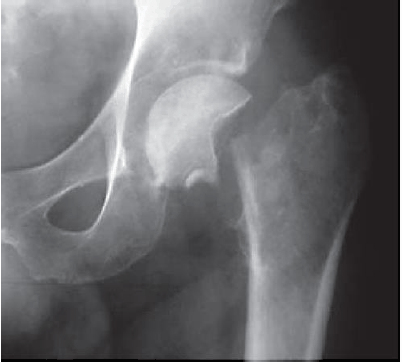

A imagem abaixo caracteriza:

Provas